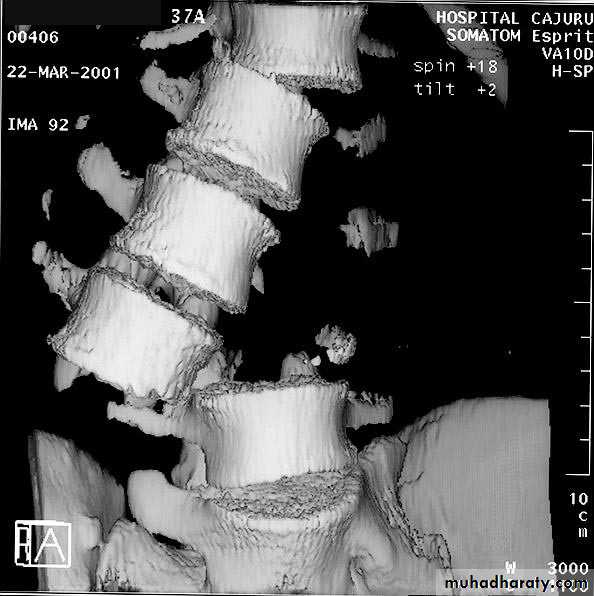

CT: best for bony anatomy.

Thoraco-Lumbar fractures

50% of injuries occur at Thoraco-lumbar junction.

Common fractures:

Wedge fracture (flexion/compression).

Burst (compression).

Chance (flexion/distraction).